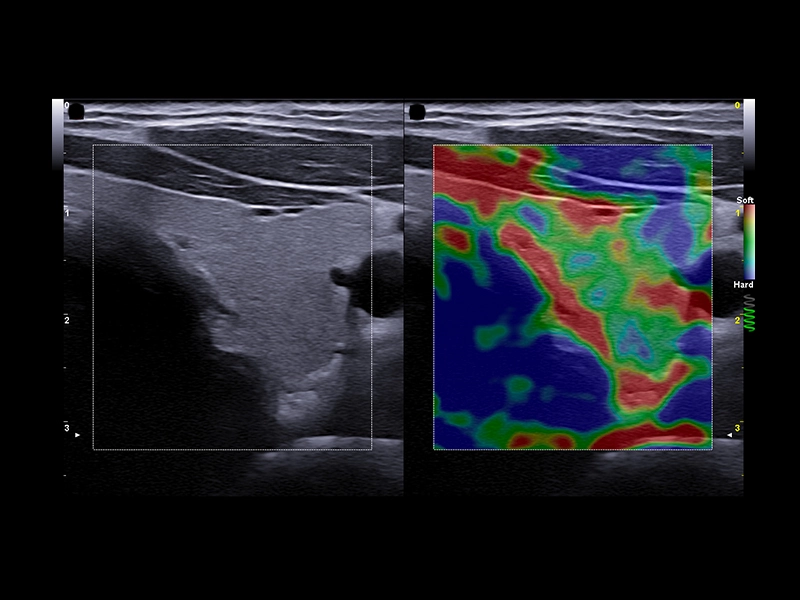

MyLab™9 Platform - Elastography advanced measurement package on breast lesion

MyLab™9 Platform - Elastography advanced measurement package on breast lesion